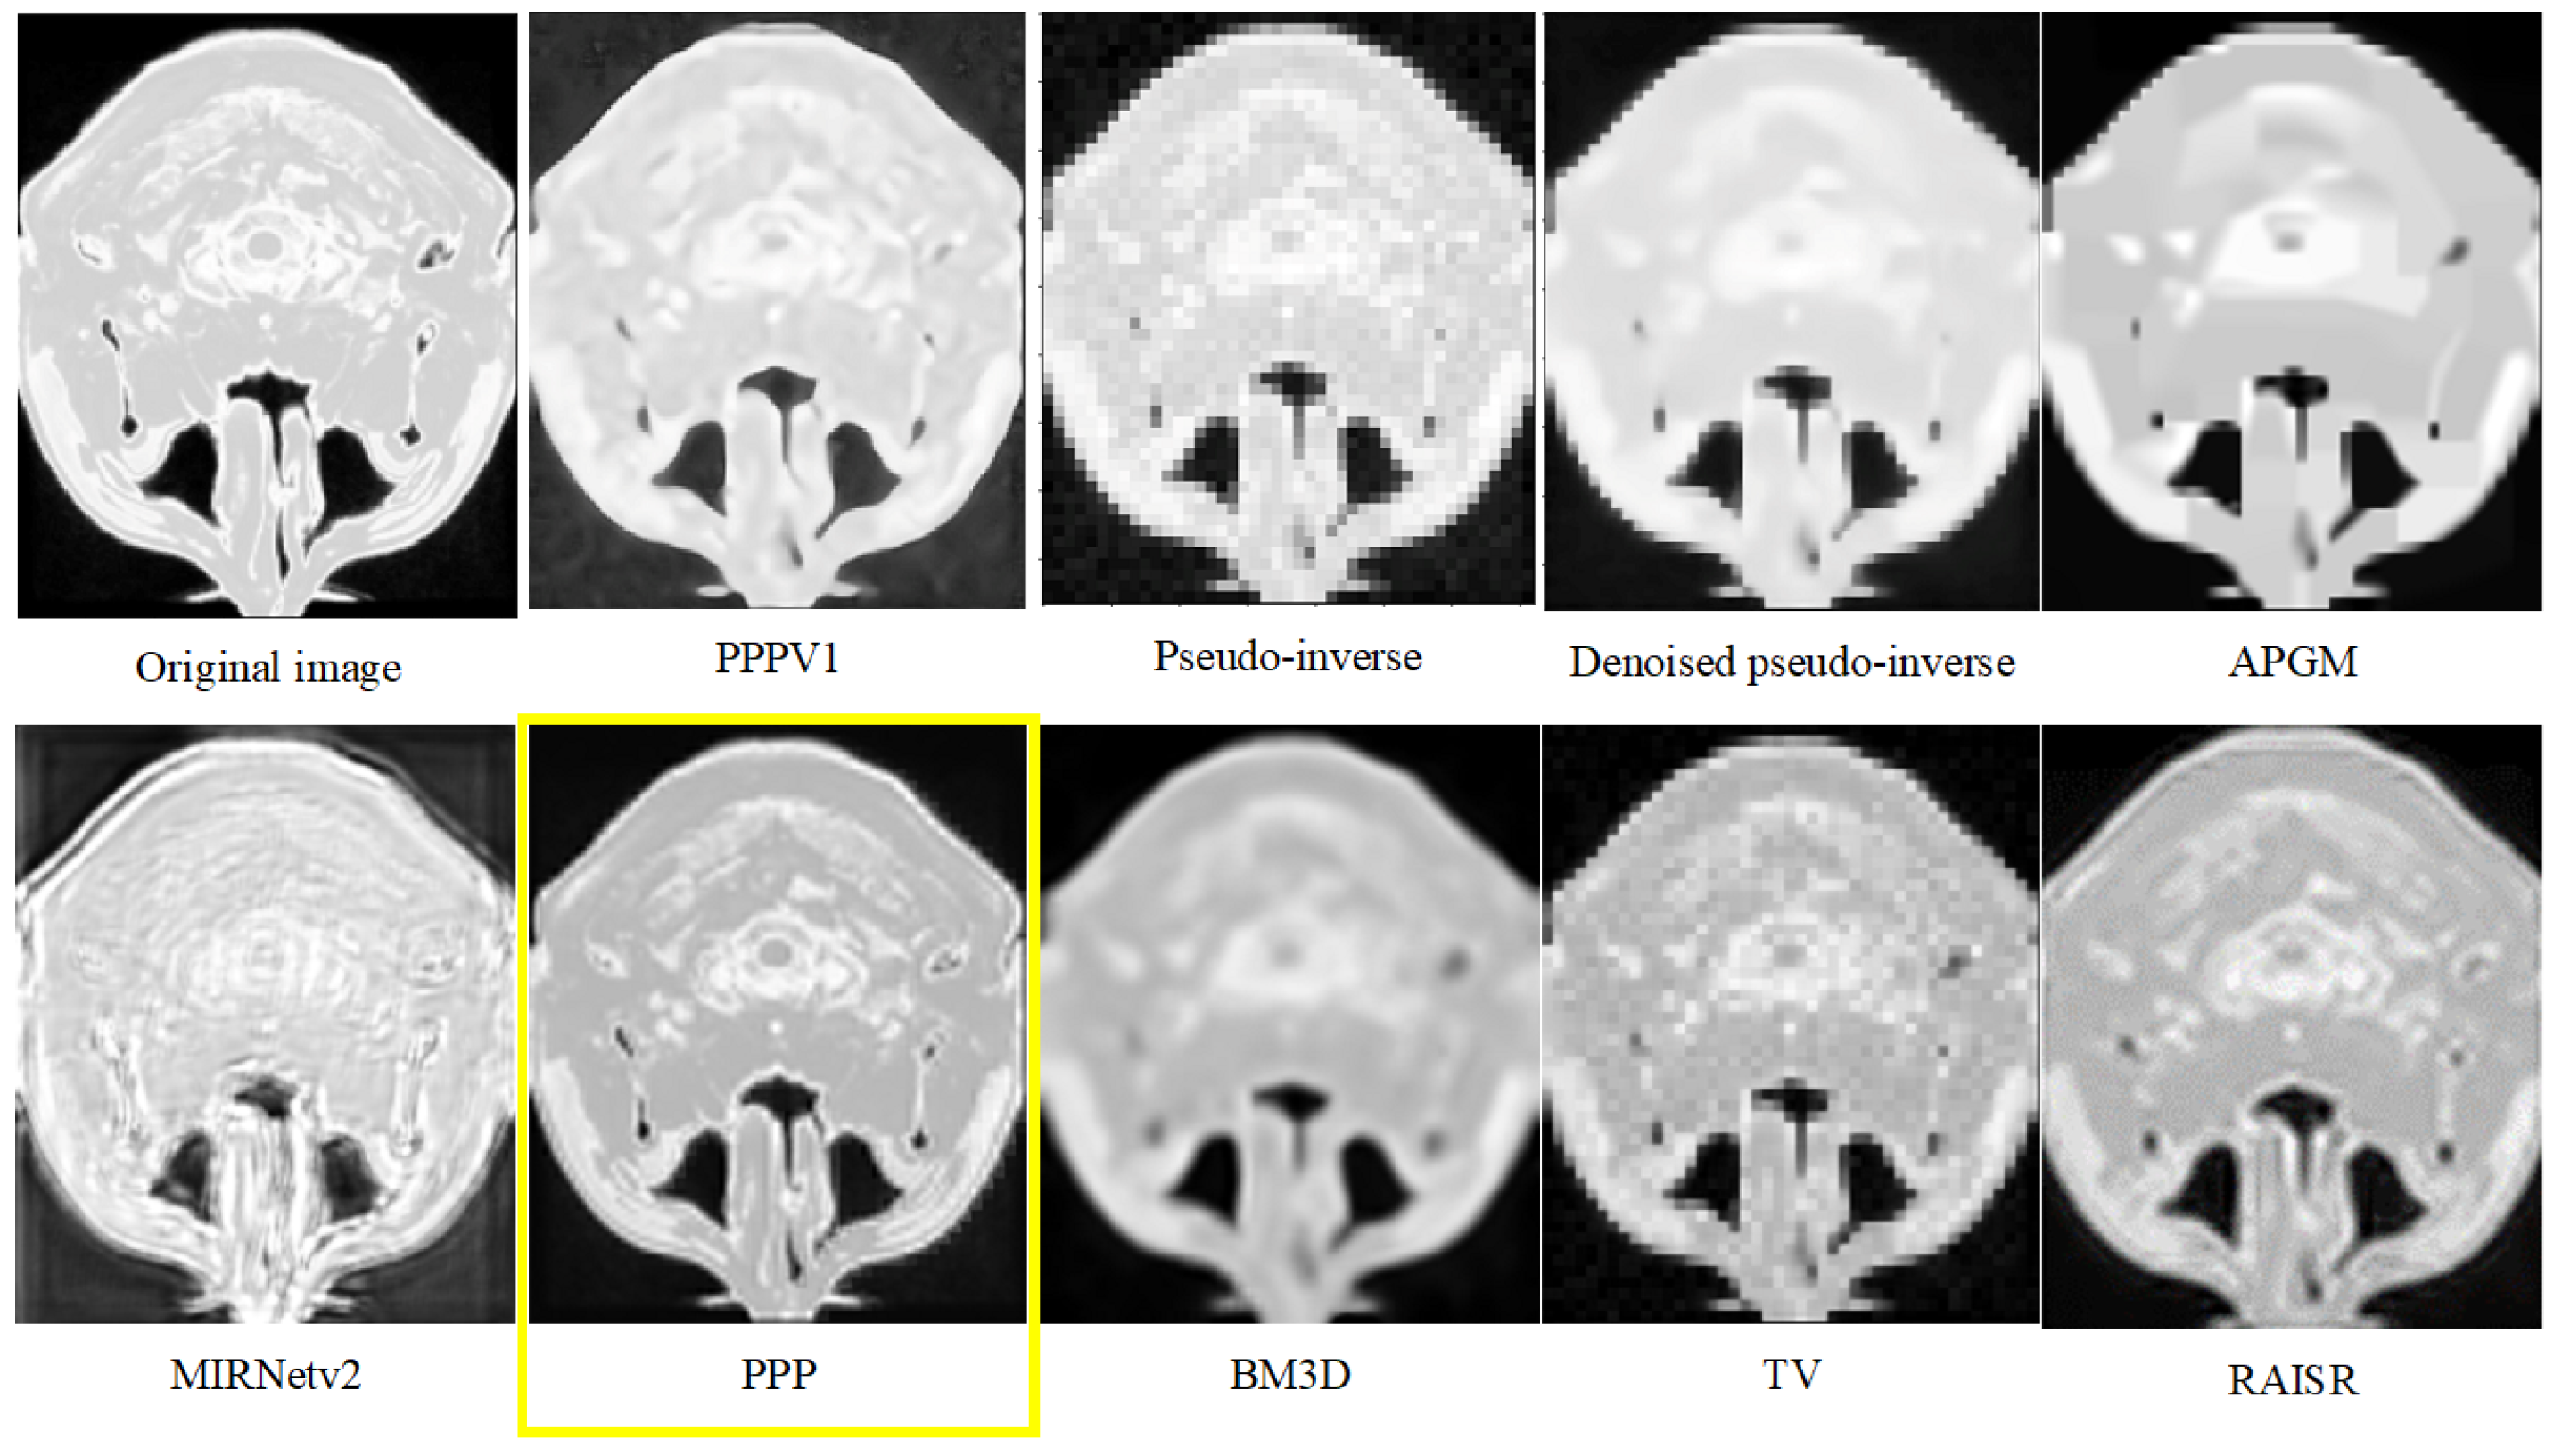

- The experimental results demonstrate the superiority of our approach over existing techniques, underscoring its potential for clinical applications in neuroimaging.

- The practical implications of our results suggest that our method holds great promise for applications where MRI slices quality enhancement is paramount.